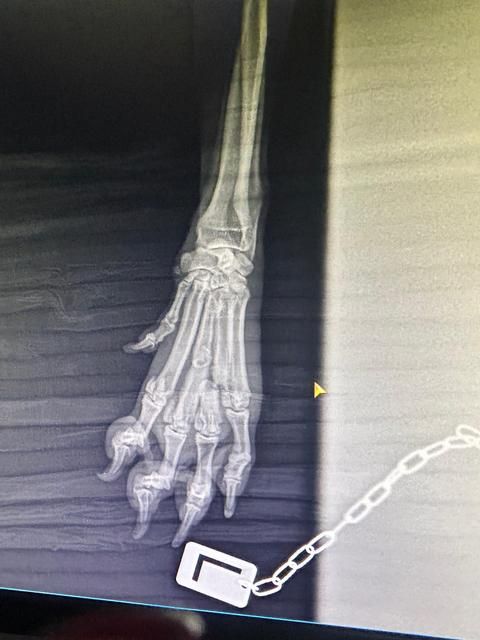

In der Tierklinik angekommen, wurde sie gründlich untersucht. Sie war stark entkräftet, ausgehungert und hat einige gebrochene Zehen. Glücklicherweise scheint es so, dass ihre Pfoten ohne Operation heilen können – sie muss jedoch eine Weile ruhig im Käfig gehalten werden, damit alles wieder richtig zusammenwächst.